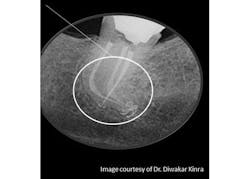

Successful root canal therapy is dependent on many factors, based on decisions made by the clinician from start to finish of each case. There are many different obturation techniques; no one technique has been identified as clearly superior. Dr. Diwakar Kinra, editorial director of DE’s ENDO File, talks through the concept of obturation in endodontics and shares his insight into the ongoing controversy. Click here to read the article